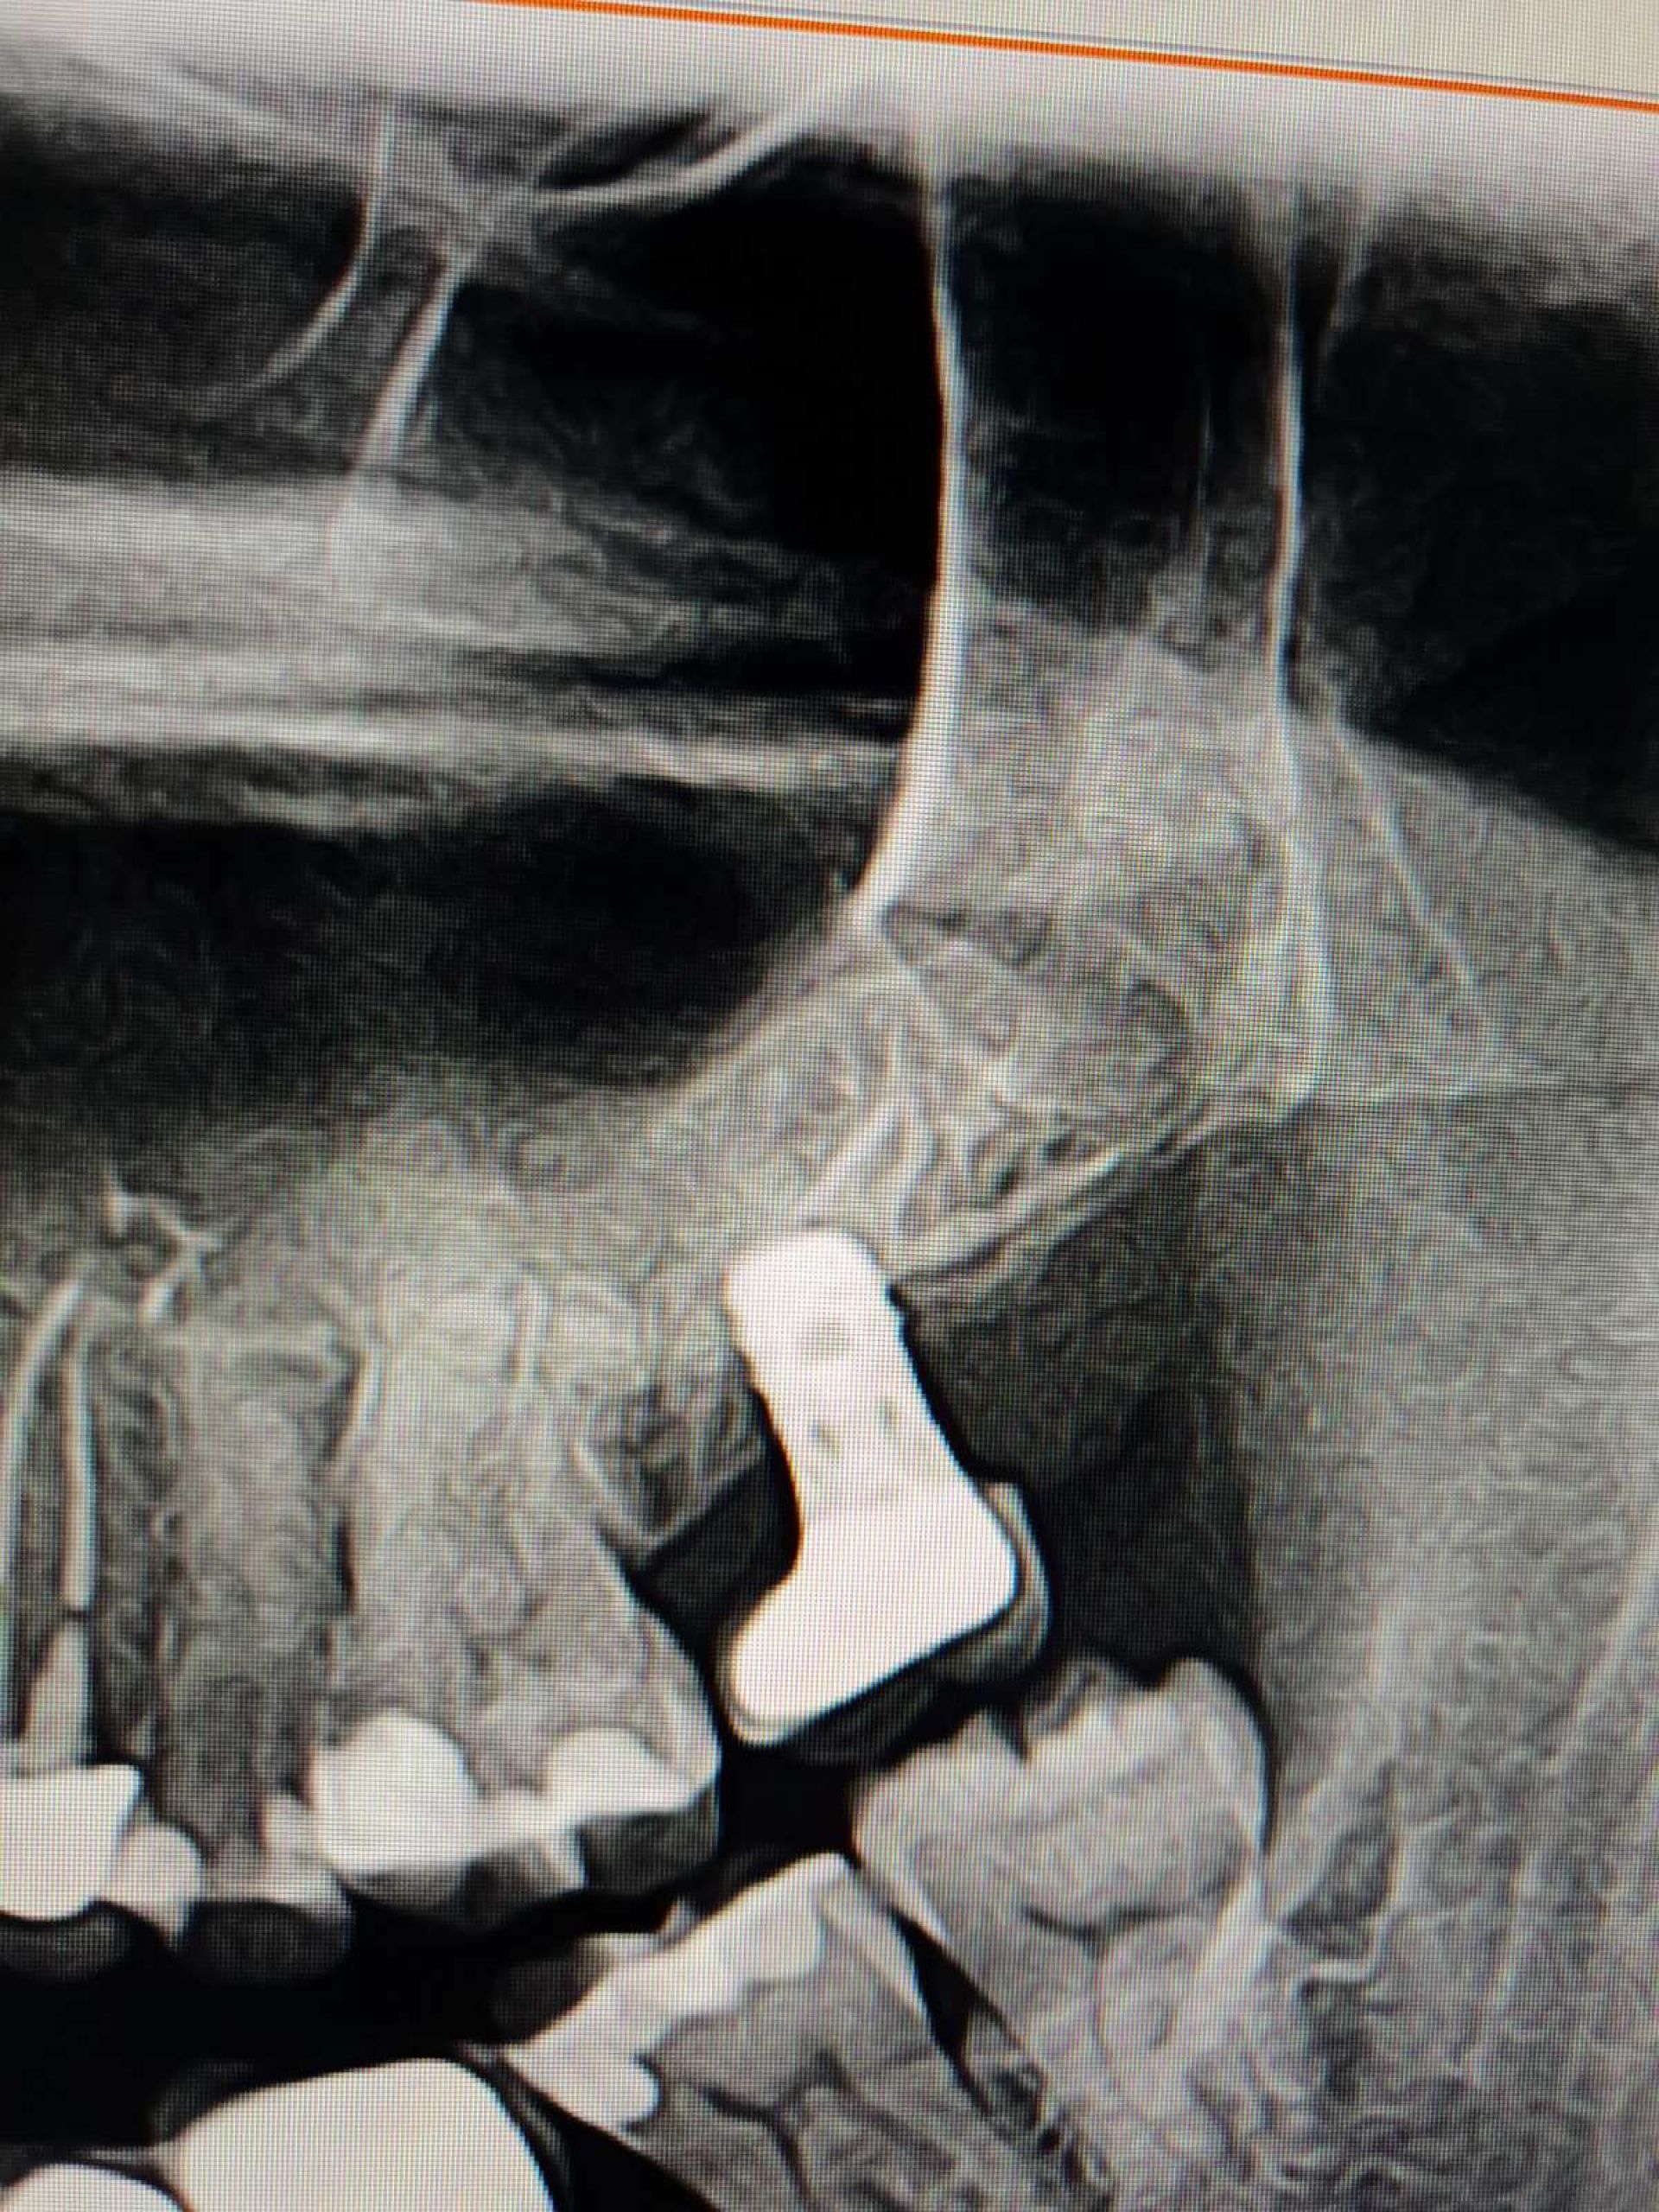

Ще один важливий фактор, який вигідно відрізняє клініку INNOVA від конкурентів – власний комп'ютерний томограф. Таким чином, можливо провести комплексну діагностику перед плануванням операції. Дані КТ зубів дозволяють не лише оцінити стан кістки пацієнта, а також дозволяють виготовити спеціальні хірургічні шаблони для майбутньої операції та оцінити становище імплантату відразу після операції.

Техніка одномоментної імплантації: сучасна методика, під час якої встановлення імпланту проходить одразу після видалення зуба. Фактично, дві складні процедури (видалення зуба і встановлення імпланту) виконується за один візит, Але у випадках, коли пацієнт потребує відновлення давно втрачених зубів, лікар розглядатиме інші техніки.

В МНВЦ "Плоскирів" найголовнішим критерієм є якіст послуг і для цього у них є все: досвідчені лікарі, кращі матеріали, найсучасніші цифрові 3D-технології, обладнання та власна зубопротезна лабораторія.